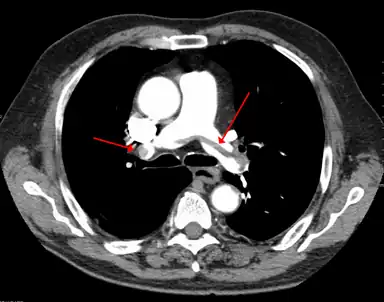

A pulmonary embolism (PE) occurs when a blood clot from a deep vein (a DVT) detaches from a vein (embolizes), travels through the right side of the heart, and becomes lodged as an embolus in a pulmonary artery that supplies deoxygenated blood to the lungs for oxygenation.[28] Up to one-fourth of PE cases are thought to result in sudden death.[12] When not fatal, PE can cause symptoms such as sudden onset shortness of breath or chest pain, coughing up blood (hemoptysis), and fainting (syncope).[29][30] The chest pain can be pleuritic (worsened by deep breaths)[29] and can vary based upon where the embolus is lodged in the lungs. An estimated 30–50% of those with PE have detectable DVT by compression ultrasound.[30]

DVT is most frequently a disease of older age that occurs in the context of nursing homes, hospitals, and active cancer.[3] It is associated with a 30-day mortality rate of about 6%, with PE being the cause of most of these deaths.[1] Proximal DVT is frequently associated with PE, unlike distal DVT, which is rarely if ever associated with PE.[39] Around 56% of those with proximal DVT also have PE, although a chest CT is not needed simply because of the presence of DVT.[1] If proximal DVT is left untreated, in the following 3 months approximately half of people will experience symptomatic PE.[9]